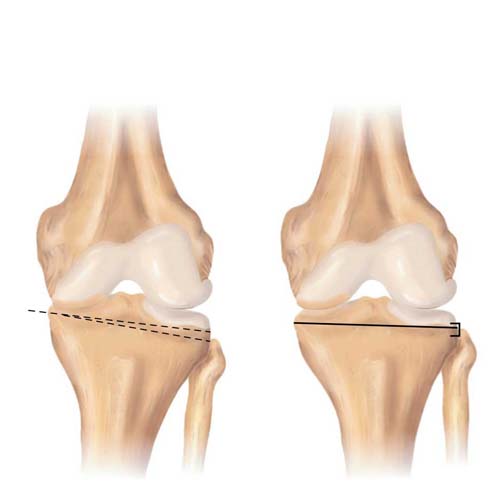

قیمت: 52٬500 تومان - دسته بندی فایل: پاورپوینتدانلود پاورپوینت جراحی استئوتومی زانو

خرید پاورپوینت حرفه ای با موضوع جراحی استئوتومی زانو از لوکس فایل